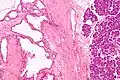

![]() | |

| Micrograph showing a pancreatic serous cystadenoma. H&E stain. | |